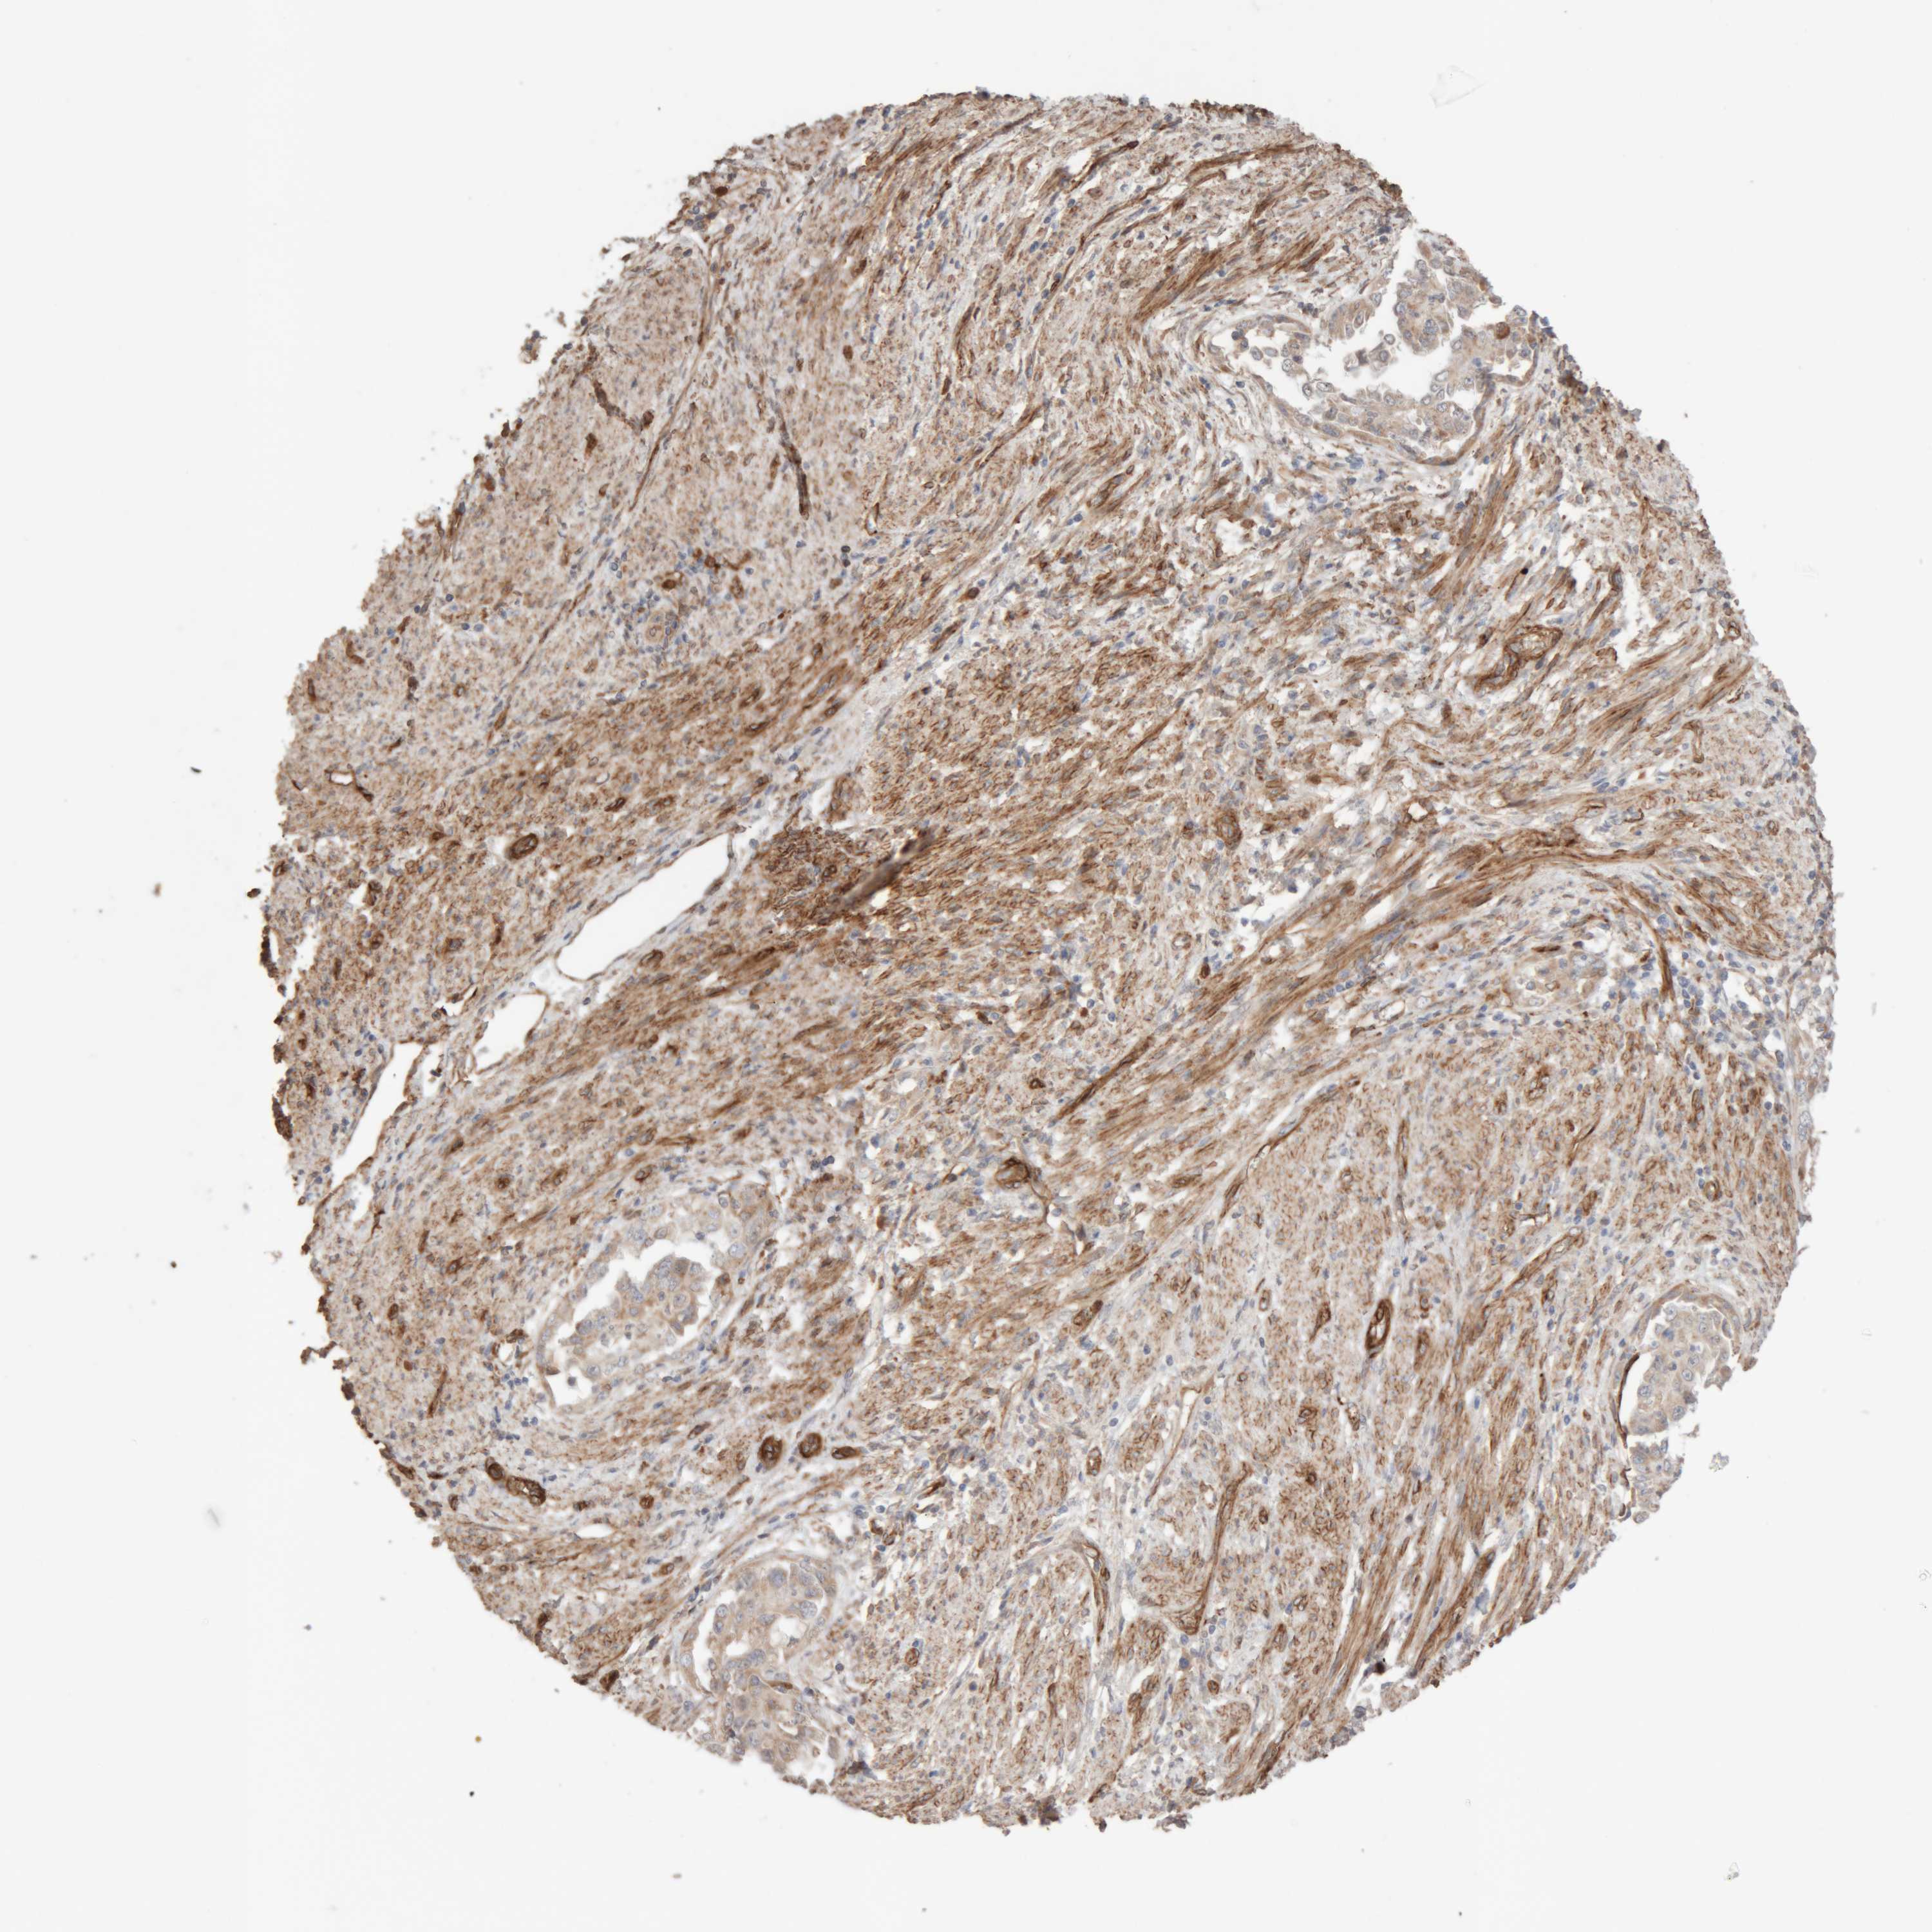

ENDOMETRIAL CANCER - Protein expressioni

A mouse-over function shows sample information and annotation data. Click on an image to view it in a full screen mode. Samples can be filtered based on level of antibody staining by selecting one or several of the following categories: high, medium, low and not detected. The assay and annotation is described here.

Note that samples used for immunohistochemistry by the Human Protein Atlas do not correspond to samples in the TCGA dataset.

Antibody stainingi

Antibody staining in the annotated cell types in the current human tissue is reported as not detected, low, medium, or high, based on conventional immunohistochemistry profiling in selected tissues. This score is based on the combination of the staining intensity and fraction of stained cells.

Each image is clickable and will lead to virtual microscopy that enables deeper exploration of all samples and also displays staining intensity scores, fraction scores and subcellular localization as well as patient and tissue information for each sample.

Antibody HPA025731

Staining

High

Medium

Low

Not detected

Intensity

Strong

Moderate

Weak

Negative

Quantity

>75%

75%-25%

<25%

None

Location

Nuclear

Cytoplasmic/membranous

Cytoplasmic/membranous,nuclear

Adenocarcinoma, NOS

Adenocarcinoma, metastatic, NOS